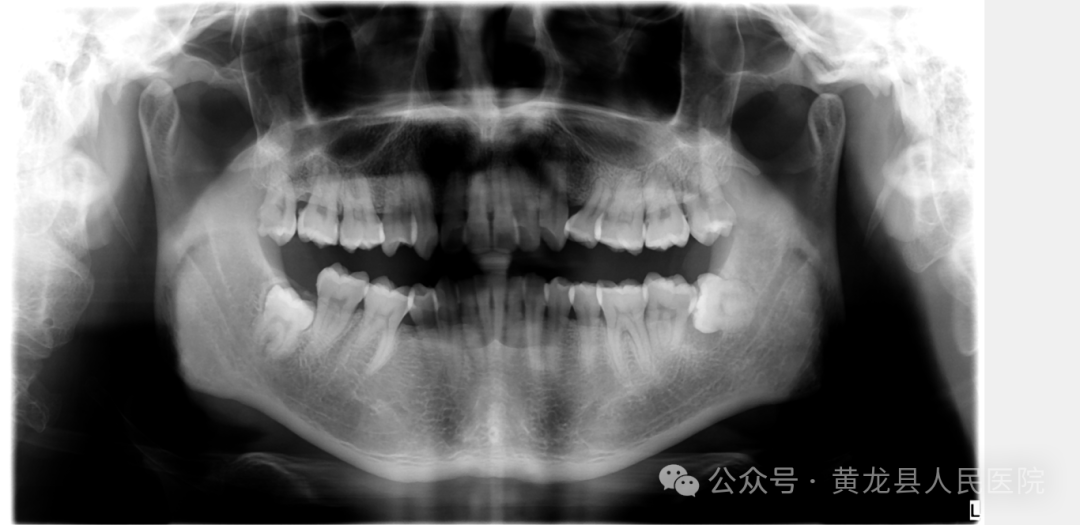

常见的牙科放射检查包括曲面体层片( 全景片 )、小牙片、头颅正侧位片、全头颅 CT、 CBCT 、根管CT等。

由于牙齿下部隐藏在牙槽骨中,口腔医生要了解牙齿的整体情况就需要拍摄全景片;要了解个别牙根及周围变化,则选择拍摄小牙片或根管CT。医生要判断牙槽骨是否符合种植条件,或者了解埋伏阻生齿的三维位置以及其他颌骨内病变组织的形态大小时,则需要进一步拍摄 CBCT 。